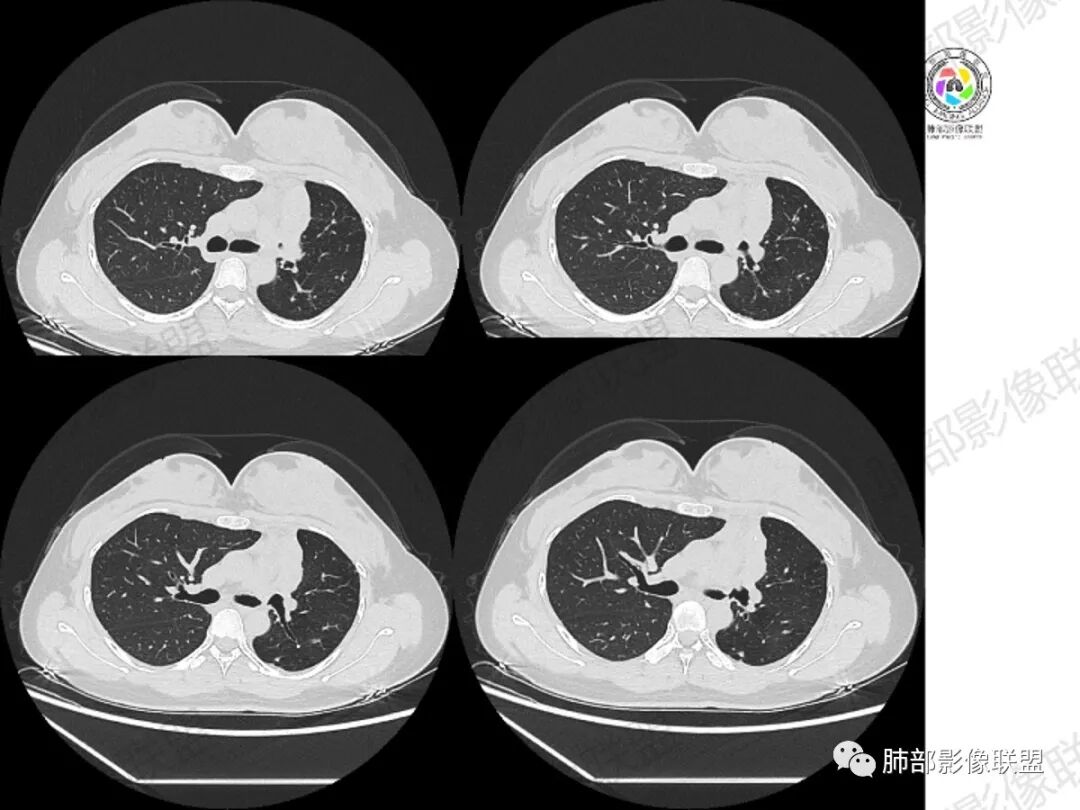

年轻女性,咳嗽咳痰一个月,左肺体积缩小,左肺尖部胸膜下实变影,宽基底与胸膜相贴,病灶边缘平直收缩,部分略膨隆,病灶下方可见支气管挤压,肺窗所示:周围伴有多发结节部分可见树丫征,纵隔窗可见病灶与纵隔胸膜黏连,部分与左肺动脉分界欠清,平扫密度尚均匀,增强扫描不均匀强化,内部可见多个低密度坏死,伴有条状血管影,纵隔淋巴结略有肿大。

胸部CT:左肺体积缩小,左肺上叶前段纵隔旁胸膜下大片实变影,边缘清楚、匀齐、平直收缩,部分略膨隆,周围多发结节、树芽卫星灶,纵隔窗病灶与纵隔胸膜黏连,实变内多发点状钙化。平扫密度尚均匀,增强扫描不均匀明显强化,多个低密度区,呈仙人掌样,伴有条状血管影,考虑慢性炎症伴左上叶前段支气管闭塞,TB?鉴别黏表、腺癌等。

青年女性,咳嗽、咳痰、痰中带血1月余,左肺上叶纵隔旁团片影,边缘见平直、U型凹陷,边缘以收缩为主,部分膨隆,内有点状钙化,增强见支气管粘液栓,病灶近端见坏死。周围少许小点状影(考虑卫星灶可能),首先考虑结核,鉴别粘表。

青年女性、痰血症状一月,左胸廓缩小,左上肺固有段支气管狭窄堵塞,前段支气管扩张伴粘液栓、远侧肺不张,肿块整体呈梭形沿前段支气管爬行向外延伸,内可见多处圆形低密度坏死灶,肺不张处血管造影强化明显,周围散发束状细小结节灶,肺门及纵隔淋巴结尚正常。考虑结核可能大。